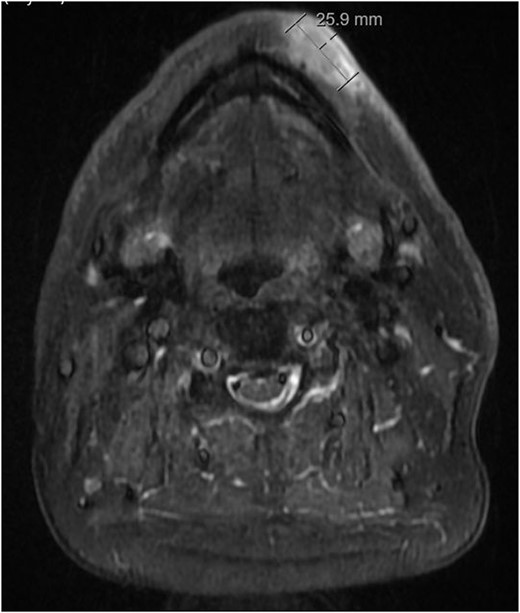

Post-review, he was listed for an urgent biopsy under local anaesthetic. Histology showed well-to-moderately differentiated adenocarcinoma, with the likely primary being upper gastrointestinal or pancreatic in origin. Positive immunostaining was noted for CK7 and negative for p63, TTF-1, Napsin, CK20 and PSA. Magnetic resonance imaging (MRI) of the face and neck showed a 2.6-cm lesion on the chin invading subcutaneous tissues, with no mandibular involvement (Fig. 1). Due to the nature of the histology results, he underwent a positron emission tomography(PET)-computed tomography (CT) scan, which showed a cystic area in the pancreatic tail, alluding to a pancreatic adenocarcinoma primary. Widespread metastases noted included multifocal liver metastases, peritoneal lymph node, muscle and bony involvement (Figs 2–4).